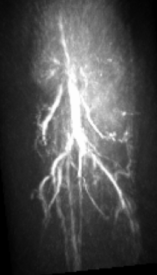

The maximum intensity projection (MIP) of the 3D mouse images reconstructed by use of the GPU-based implementations reveal the mouse body vasculature as shown in Fig. 7. Images reconstructed by use of both the PLS-Int and the PLS-Sph algorithms appear to have cleaner background than do the images reconstructed by use of the FBP algorithm from the same amount of data. All images reconstructed by iterative algorithms were obtained by 202020-iterations starting with uniform zeros as the initial guess. The PLS-Int algorithm took approximately a half day and 222 days to process the “quarter data” and the “full data” respectively. The PLS-Sph algorithm took approximately one day and 444 days to process the “quarter data” and the “full data” respectively. Alternatively, if the CPU-based implementations were utilized, the PLS-Int algorithm would take an estimated 686868 days and 277277277 days to process the “quarter data” and the “full data” respectively. The PLS-Sph algorithm would take an estimated 275275275 days and 1,10011001,100 days to process the “quarter data” and the “full data” respectively.